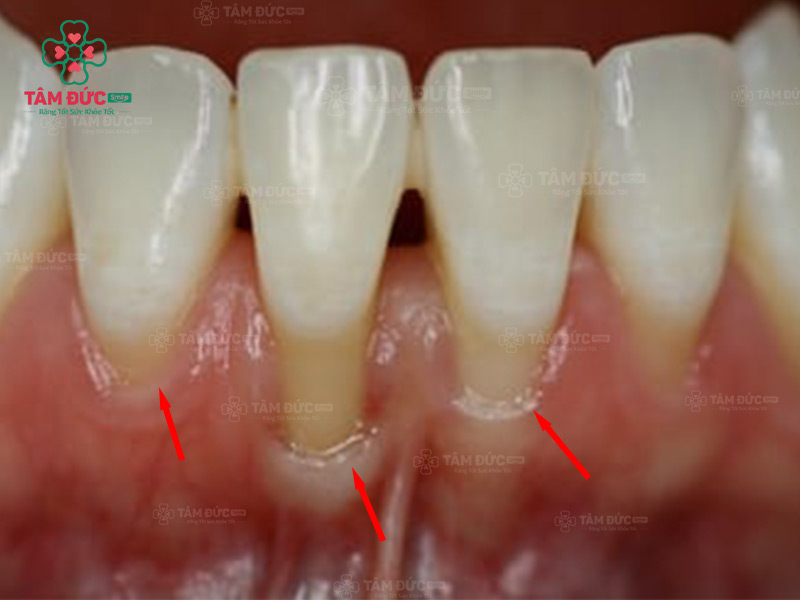

Tụt lợi là hiện tượng vùng lợi bao quanh chân răng bị tách khỏi chân răng rồi dịch chuyển xuống phần cuống răng. Tụt lợi sẽ làm thân răng bị lộ ra ngoài. Vấn đề này thường chỉ xuất hiện ở 1 vài răng, có thể xảy ra ở hàm trên hoặc hàm dưới.

Quý khách có thể nhận biết tụt lợi bằng mắt thường vì vùng lợi bị rút sâu xuống phía dưới, làm cho cổ răng lộ ra. Tuy nhiên, tụt lợi hàm dưới làm Quý khách khó phát hiện hơn, vì môi dưới đã che lấp toàn bộ chân răng và lợi. Tụt lợi sẽ làm ảnh hưởng nghiêm trọng đến thẩm mỹ nụ cười, làm cho răng nhạy cảm và suy yếu dần.

Tụt lợi làm lộ chân răng